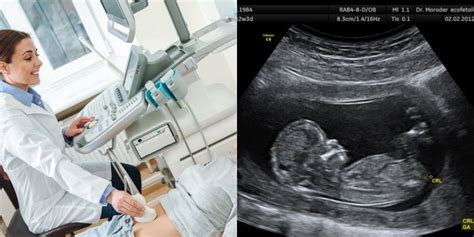

Nėštumo trukmė paprastai skaičiuojama nuo paskutinių mėnesinių pirmos dienos. Tiksliai nustatyti nėštumo amžių padeda ultragarsinis tyrimas - ypač pirmąjį trimestrą, kai vaisiaus dydis yra vienas iš patikimiausių rodiklių.